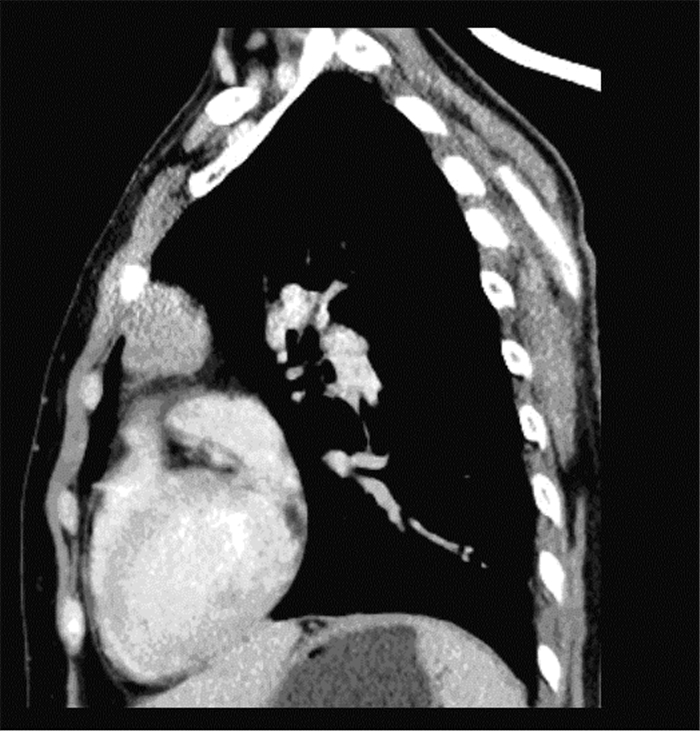

患者,女,66岁,于2016年9月28日因左前胸部隐痛10余日入院。查体时发现前纵隔占位,CT示:考虑胸腺瘤,见图 1;2016年10月13日行胸腔镜下胸腺瘤切除术,术中见肿瘤位于前纵隔内,直径5.0 cm,边界清,易剥离。病理检查:边界清,有包膜;切面灰白、灰红色,呈实性,质软,未见明显出血及坏死区;肿瘤低倍镜下境界清楚,有完整的纤维性包膜,局部可见包膜受到侵犯,见图 2A;肿瘤实性区内见上皮样肿瘤细胞呈微结节状分布,部分区域可形成条索样结构,上皮样细胞呈卵圆形或短梭形,细胞核呈卵圆形,部分可见小核仁,无明显异型性,核分裂象罕见,无明显出血及坏死,肿瘤细胞巢中可见少量淋巴细胞散在分布;肿瘤间质为大量的淋巴细胞,分割肿瘤细胞巢,部分区域可见滤泡结构形成或有生发中心出现,周围有少量薄壁血管,见图 2B。免疫表型:上皮样肿瘤细胞巢CK-pan、CK5/6、CK19阳性,EMA阴性,上皮细胞巢内可见少量CD3和CD8阳性的T细胞,间质内T细胞和B细胞均有表达,CD20、PAX-5阳性的B细胞主要位于滤泡区,见图 2C,周边为CD3、CD8阳性的T细胞;TdT阳性的未成熟T细胞主要分布于上皮样细胞巢周边的T淋巴细胞间质中;CD1a和S100可显示上皮细胞巢中散在分布朗格汉斯细胞,见图 2D;结合组织学形态和免疫组织化学结果,诊断为:伴淋巴样间质的微结节型胸腺瘤。术后6天恢复良好办理出院。